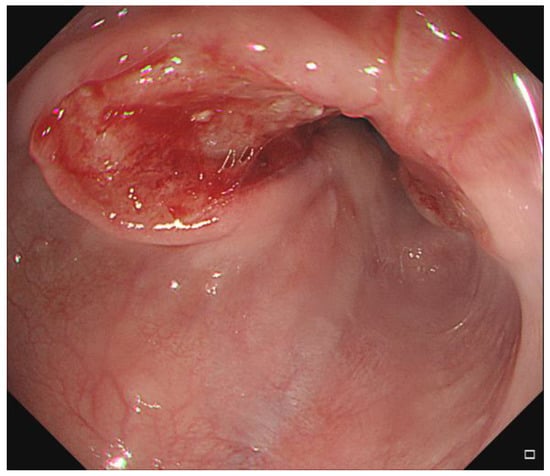

A 79-year-old man was diagnosed with esophageal cancer during an evaluation of dysphagia. Upper endoscopy revealed a lumen-encircling mass 32 cm from the incisors (Figure 1); a biopsy specimen revealed squamous cell carcinoma. Distal esophageal wall thickening and multiple metastatic lymph nodes were observed upon computed tomography (CT) of the chest and abdomen (Figure 2A,B). The esophageal cancer stage was T4N2M0.

Definitive concurrent chemoradiation was scheduled. The radiation dose was 50.4 Gy/28 fractions over 5.5 weeks. The patient had received continuous infusion of 5-fluorouracil (1000 mg/m2) on days 1 through 4 and days 22 through 25 and cisplatin (75 mg/m2) was given on days 1 and 22. By 3 weeks after commencement of chemoradiation, the esophagus was outside of the radiotherapy field during image-guided radiotherapy. Follow-up CT revealed that the esophagus had moved from the right of the aorta to the left (Figure 2C,D). Fusion of the radiation plan and follow-up CT showed that prescription dose did not cover the entire esophagus (Figure 3).

Figure 2. Distal esophageal wall thickening (arrow) was found on axial view (A) and coronal view (B) of initial computed tomography (CT) scan. Metastatic lymph nodes were not seen on these CT slices. Follow-up computed tomography revealed that the esophagus had moved from the right of the aorta to the left on axial view (C) and coronal view (D) (arrow).